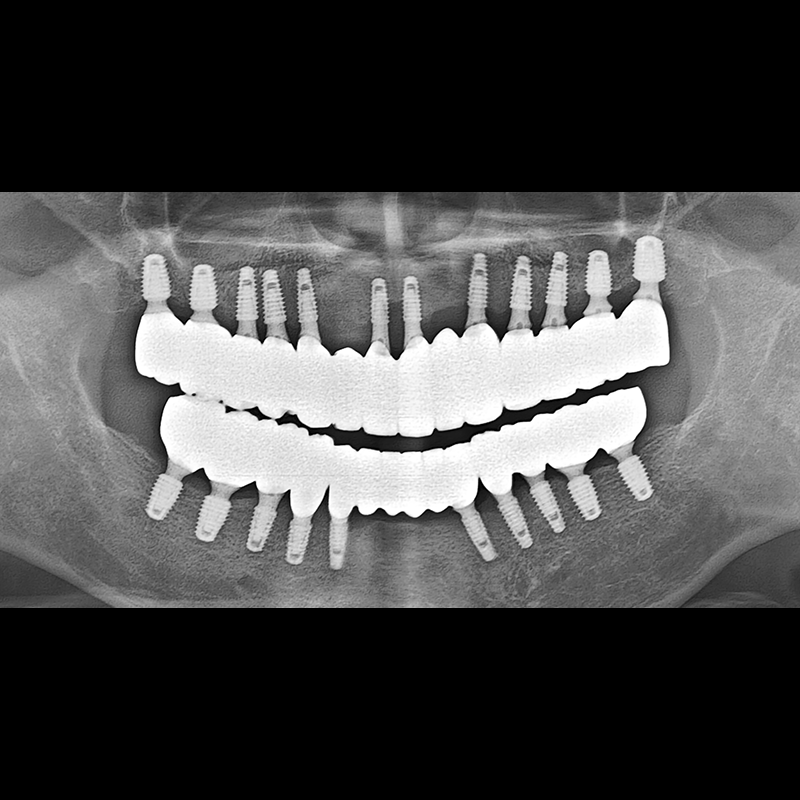

BEFORE AFTER

种植牙前后的照片 2025.05.30

在缺失的牙齿部分和难以挽救的牙齿位置植入了种植牙。